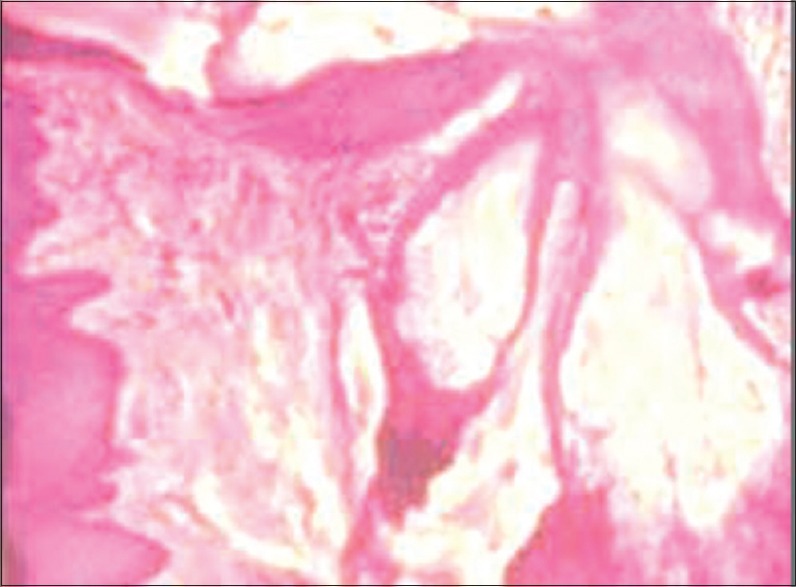

On histological examination, hyperkeratinized stratified squamous epithelium overlying dense connective tissue stroma was reported. The epithelium showed areas of keratin plugging along with collection of sebaceous glands in subepithelial regions. These lobules contained undifferentiated cells in the periphery and mature sebocytes with clear cytoplasm in the centre. Sheets, islands and cystic spaces of squamous epithelial cells and sebaceous cells were seen, without any cellular atypia or mitosis [Figure 2]. Underlying connective tissue was dense fibrous and collagenous containing numerous blood vessels along with areas of adipose tissue. Based on histological appearance, diagnosis of fibroepithelial hyperplasia with ectopic sebaceous gland and keratotic plugging was given.

| Figure 2:An area of keratotic plugging along with invaginating hyperplastic epithelium, collection of sebaceous glands in the subepithelial region with multiple lobules seen to be opening into a single duct